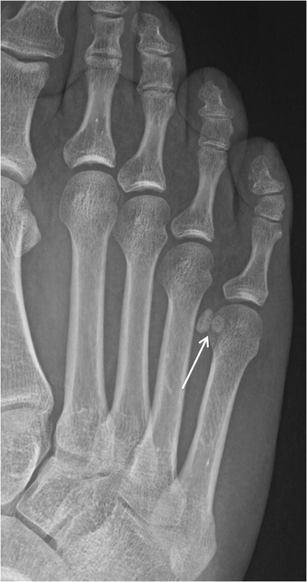

Os intermetatarseum. Oblique radiographs of the foot from two different patients show rounded (a) and spindle (b) configurations of the os intermetatarseum (arrows) located between the base of the first and second metatarsals. This may sometimes be mistaken for a bone fragment secondary to a remote trauma